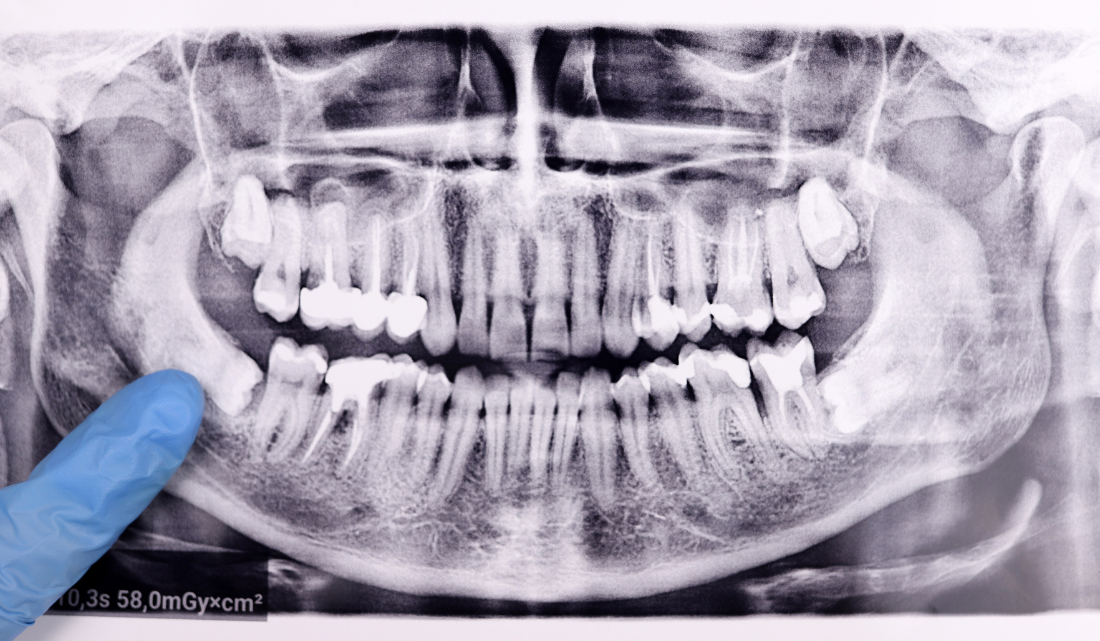

Me quitan los brackets: Todo sobre la retirada y cuidados post-tratamiento La retirada de brackets es un momento clave en el tratamiento de ortodoncia, ya que marca el final de